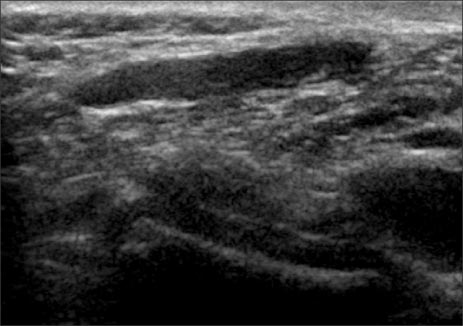

Fig. 2

Perineal ultrasonography reveals hypoechoic tubular mass without any communication between the mass and other organ.

Fig. 2 Perineal ultrasonography reveals hypoechoic tubular mass without any communication between the mass and other organ.